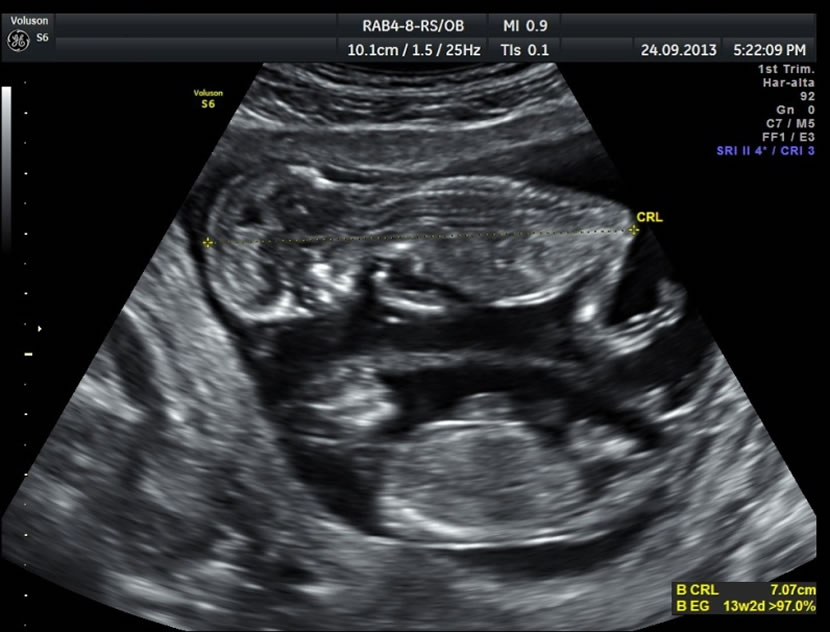

- Datar adecuadamente el embarazo